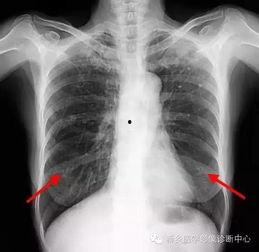

首先,得先弄清楚什么是胸片。胸片,顾名思义,就是通过X射线对人体胸部进行拍摄的一种医学影像检查。它能够清晰地显示出心脏、肺部、纵隔等器官的结构和形态,对于诊断各种胸部疾病有着至关重要的作用。

胸片检查是诊断肺部疾病的重要手段。通过观察肺部影像,医生可以初步判断患者是否患有肺炎、肺结核、肺癌等疾病。

胸片检查还可以用于诊断心脏疾病,如心包积液、心脏增大等。

对于胸部外伤患者,胸片检查可以迅速判断伤情,为医生提供治疗依据。